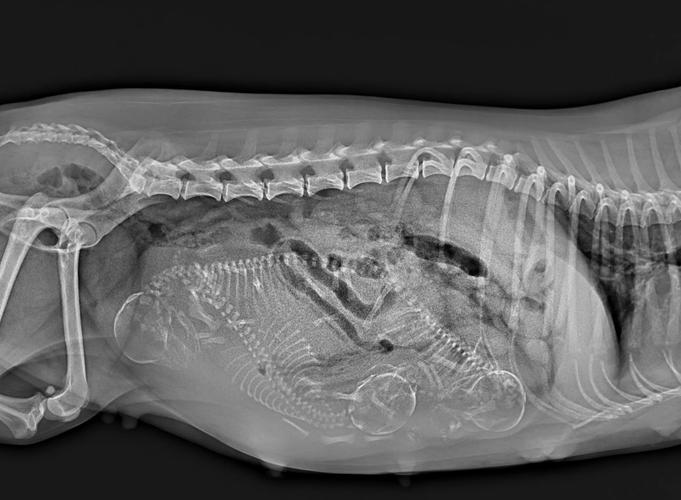

(图片来源网络,侵删)- 前45天(孕早期): 这是胎儿器官形成的关键时期,母犬的激素水平不稳定,流产风险较高。不建议在此期间给金毛洗澡,除非它非常脏或有特殊情况,并且必须由兽医指导。

- 45天到分娩前(孕中期): 这是相对安全的洗澡窗口期,此时胎儿已经基本发育成型,流产风险降低,洗澡可以帮助清洁身体,缓解孕期的不适。

- 分娩前1周: 强烈建议给母犬洗一次澡,这被称为“产前澡”,因为分娩后母犬需要专心哺乳,至少在产后1-2周内都不能洗澡,以免着凉或引发子宫感染,提前洗好澡,能让它在产后保持相对的清洁舒适。